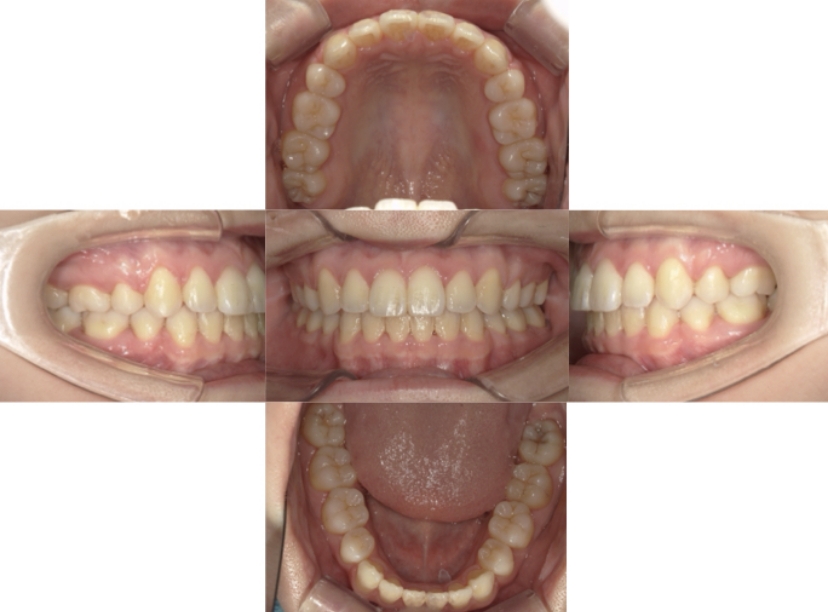

症例2

上下顎前突、叢生

抜歯

ブラケット矯正

上下顎前突、叢生(上下出っ歯、上下の前歯のガタガタ)のケースです。

装置はラビアル(上下表側)で、上下顎の小臼歯を4本抜歯を行っています。抜歯したスペースを使って、上下の前歯の後方移動と叢生(ガタガタ)の改善を行っています。

主訴 前歯のガタガタと口元がでているのが気になる。

年齢・性別 30歳 女性

お住まいの地域 東京都大田区

治療方針 抜歯スペースを利用して上前歯の叢生(ガタガタ)と口元突出の改善

抜歯部位 上下顎左右第一小臼歯

使用装置 ラビアル(上下表側)、顎間ゴム

治療期間 1年11か月

治療回数 13回

リテーナー クリアリテーナー

BEFORE

AFTER